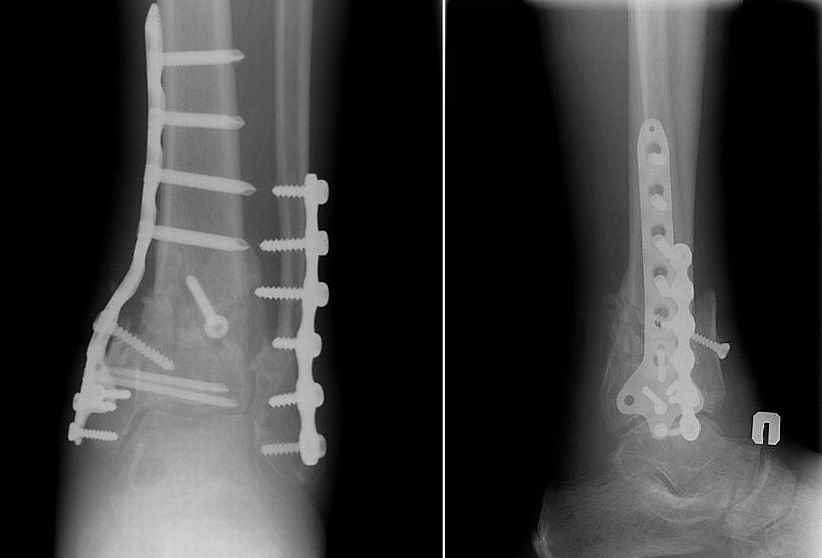

Прооперировали 6 февраля.

На операции - несращение проксимального диафизарного отломка и осколков эпифиза, которые представляли собой неправильно сросшийся, крепкий конгломерат. С учетом сохранности движений в голеностопном суставе (боясь ему навредить), решено было не разбирать их, а только исправить ось голени, что и было сделано, после остеотомии и резекции малоберцовой кости + остеопластика.

Получилось видимо не идеально, внушает оптимизм хорошее состояние мягких тканей и сохранность движений в голеностопном суставе после операции. Хотя... :)